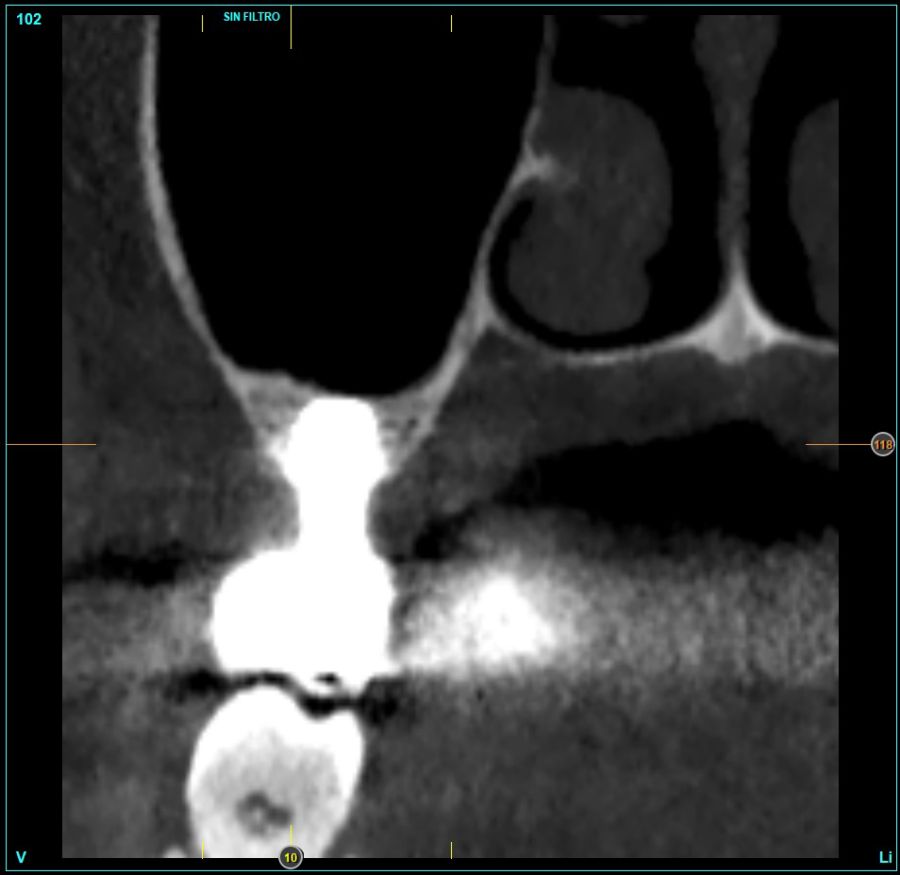

In all cases, a diagnosis was made based on study models, intraoral examination of the patient and performing a Cone-beam analysed using the specific BTI-Scan 3 software (Biotechnology Institute, Vitoria, Alava, Spain).

Patients attend subsequent check-ups performing a control Cone-Beam after 5 months (before loading the implant) and after one year of the load, performing a new measurement in these images to analyse the bone gain and the maintenance of the same. In these check-ups, data are collected on prosthetic complications or crestal bone loss in these patients, as well as possible failures.

Figures 2-19 show one of the cases included in the study.